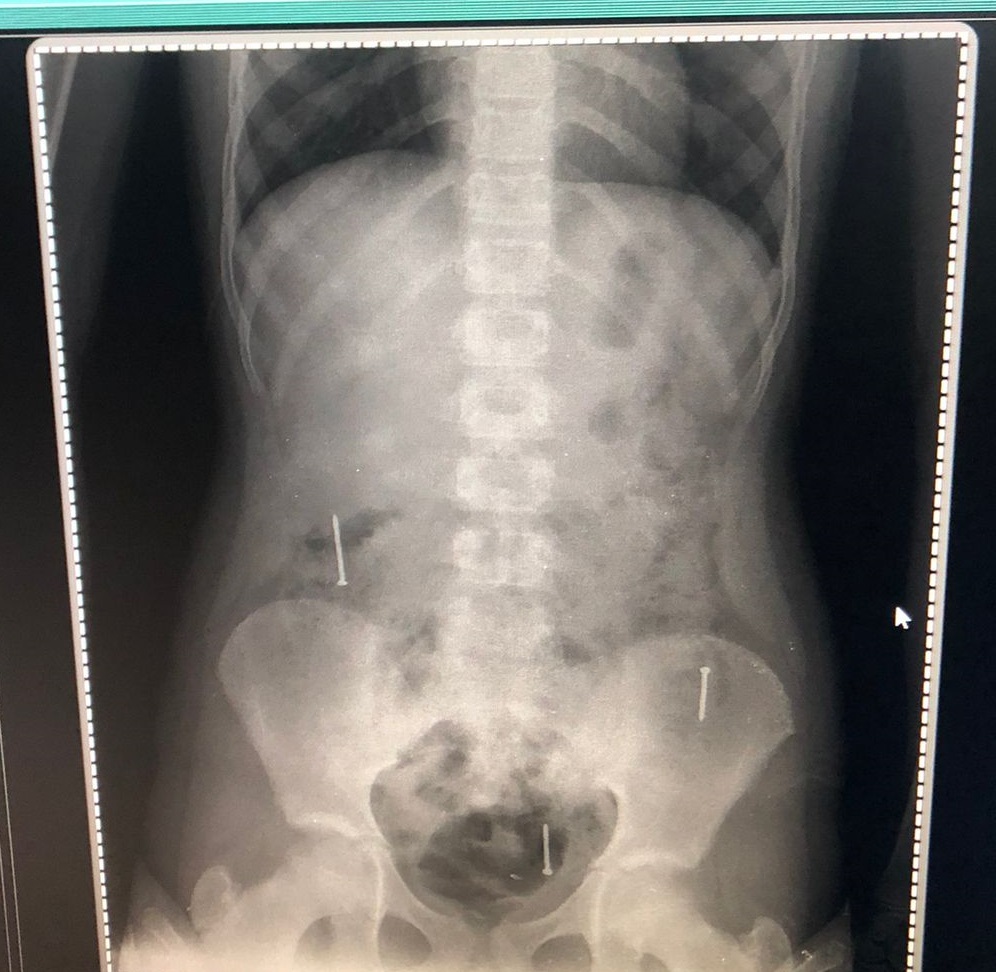

El pasado viernes ingresó al Hospital Regional de Concepción por dolor abdominal y tras una inspección médica detectaron tres clavos en su organismo, expresó...